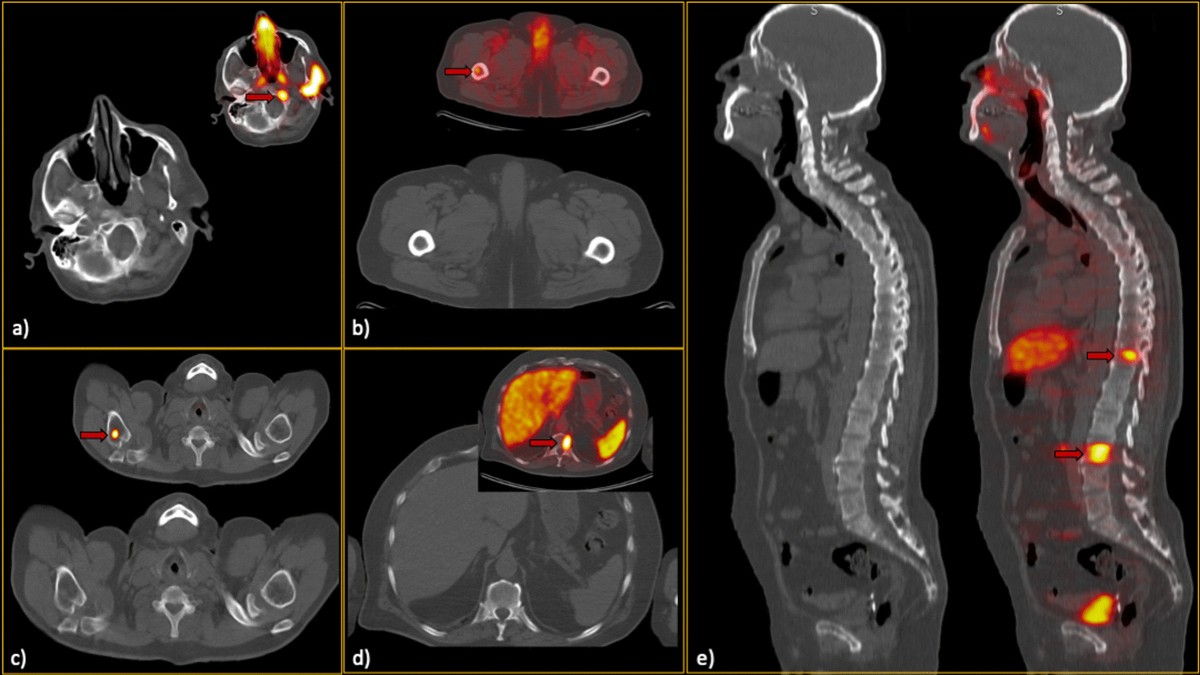

Prostate cancer metastasis to calcaneus: a solitary lesion at an atypical site, dormant for more than 10 years - Michael T McCarthy, Hawa Ebrahem, Zariena Aibdeen, Philip A Hodnett, Elizabeth Mulcahy, Nemer

image size: 2821x2806